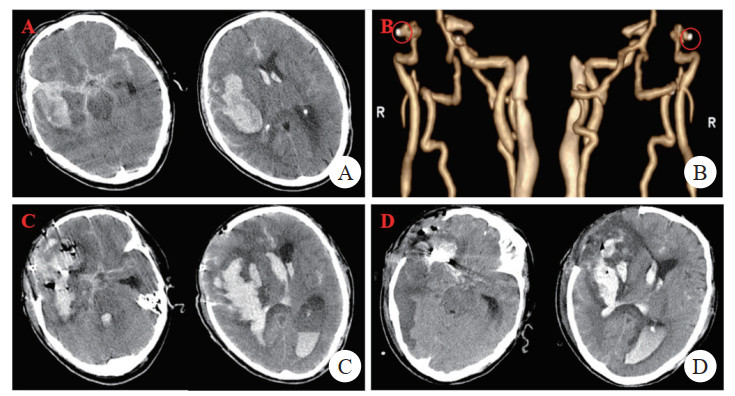

患者男,78岁,因“突发口齿不清,左侧肢体活动障碍3 d”于2023年7月16日入院。患者3 d前突发口齿不清,左侧肢体活动障碍,伴恶心呕吐,意识不清。至当地医院查头颅CT:右侧额颞叶大块血肿破入脑室系统,广泛蛛网膜下腔出血(图 1A);脑动脉CT血管造影:右侧大脑中动脉M1段动脉瘤考虑(图 1B)。于2023年7月13日急诊行“开颅动脉瘤夹闭+脑内血肿清除+去骨瓣减压术”。次日复查头颅CT:右侧颅内动脉瘤术后,右侧额颞叶血肿,脑室系统积血,蛛网膜下腔出血,局部脑膜脑膨出(图 1C)。再次急诊行“脑内血肿清除术”,查脑脊液:潘氏试验(+++),有核细胞计数4 870×106/L,中性粒细胞85%,红细胞1 826 080×106/L,葡萄糖0.95 mmol/L,氯124.2 mmol/L,腺苷脱氨酶14 U/L,蛋白含量383.2 mg/dL(表 1)。术后予美罗培南抗感染、甘露醇降颅压等治疗,患者术后出现持续发热,最高体温39.5℃,神志深昏迷,GCS 1T1,于2023年7月16日转至本院。既往有“糖尿病、高血压”病史10年余(具体不详)。拟“脑动脉瘤破裂伴蛛网膜下腔出血,颅内感染”收住重症医学科。

(A)头颅CT(2023-07-13):右侧额颞叶血肿破入脑室系统,广泛蛛网膜下腔出血;(B)脑动脉CT血管成像(2023-07-13):右侧大脑中动脉M1段动脉瘤(圆圈所示);(C)头颅CT(2023-07-14):右侧额颞叶血肿及脑室积血明显增多,中线结构明显左移,蛛网膜下腔出血稍减少;(D)头颅CT(2023-07-16):右侧额颞叶血肿及脑室积血较前减少,中线结构轻度左移,周围积液较前增多,少量蛛网膜下腔出血 图 1 患者头颅CT动态变化和脑动脉CT血管成像

入科查体:体温38.7℃,脉搏104次/min,血压142/68 mmHg(1 mmHg=0.013 kPa),呼吸15次/min,神志深昏迷,GCS 1T1,头部切口减压窗压力偏高,双侧瞳孔等大等圆,直径1.5 mm,对光反射消失,颈软,气管插管呼吸机辅助呼吸,心肺听诊无殊,四肢肌力检查不配合,病理征阴性。入院检查(2023-07-16):(1)血常规:白细胞计数7.8×109/L,中性粒细胞百分比89.5%,血红蛋白80 g/L,血小板计数95×109/L;(2)炎症指标:C反应蛋白196.7 mg/L,降钙素原1.12 ng/mL;(3)肝肾功能:谷草转氨酶20 U/L,谷丙转氨酶14 U/L,总胆红素12.1 μmol/L;白蛋白29.7 g/L,肌酐76.6 μmol/L,血糖7.99 mmol/L;(4)脑脊液检查:潘氏试验(+),有核细胞计数4 734×106/L,中性粒细胞百分比96%,葡萄糖0.01 mmol/L,氯129.3 mmol/L(表 1);头颅CT:颅脑血肿清除术+颅内动脉夹闭术后改变,术区积血/液、积气,右侧额颞叶血肿,脑室系统积血,中线结构左偏(图 1D)。